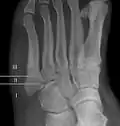

Jones fracture as seen on Xray

A Jones fracture is a broken bone in a specific part of the fifth metatarsal of the foot between the base and middle part .[8] In general, fifth metatarsal fractures heal readily, but a Jones fracture must be recognized and accurately diagnosed because of its higher rate of delayed healing or nonunion.[4] It results in pain near the midportion of the foot on the outside.[2] There may also be bruising and difficulty walking.[3] Onset is generally sudden.[4]

Diagnostic X-rays include anteroposterior, oblique, and lateral views and should be made with the foot in full flexion.